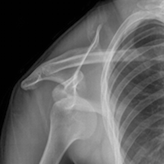

The review looked at the non‐surgical management of anterior shoulder dislocation following closed reduction, and the intervention of interest is immobilisation in external rotation. Acute anterior shoulder dislocation, where the top end of the upper arm bone is pushed out of the joint socket in a forward direction, is typically treated by closed reduction, to put the joint back, followed by a short period (3 to 6 weeks) of immobilisation and then physical therapy. The overall aim of treatment is to restore a fully functioning, painless, and stable shoulder. The importance of achieving shoulder stability is underpinned by the high rates of re‐dislocation, especially in active young adults.

The main rationale for immobilisation is to allow healing to take place. While the extent and nature of the soft‐tissue damage vary, there are common patterns of injury. Often involved is a Bankart lesion, where the fibrocartilage rim of the shoulder socket tears away from the underlying bone at the front of the joint. Increasing the contact pressure (coaptation) between the torn surfaces might facilitate healing and, ultimately, reduce recurrence. Cadaveric studies undertaken to test coaptation in different shoulder positions have had contradictory results. Using specimens whose muscles were removed, Itoi and colleagues found no difference from full internal (inwards) rotation to 30 degrees of external (outwards) rotation with the elbow at the side.[2] However, they argued that their experiment did not account for the tensioning effect of tendons at the front of the joint, nor the possibility that such tensioning might limit haematoma (blood clot) formation in the living subject. Two cadaveric studies evaluated coaptation with tendons in situ. Miller and colleagues reported increased coaptation at 45 degrees of external rotation,[3] but others were unable to replicate this in any degree of rotation, whether in intact shoulders, shoulders with surgically created Bankart lesions, or dislocated shoulders.[4] In the clinical context, magnetic resonance imaging (MRI) studies have shown better coaptation of Bankart lesions in external rotation.[5, 6] An observational arthroscopic study of patients with Bankart lesions found that external rotation improved the position of the fibrocartilage rim in most cases.[7] Considering this somewhat equivocal background, there has been considerable and sustained interest in the possibility that external rotation immobilisation (where the arm is orientated outwards with the forearm away from the chest) may improve healing, and consequently outcomes, in comparison with the traditional approach of internal rotation immobilisation (in a sling).